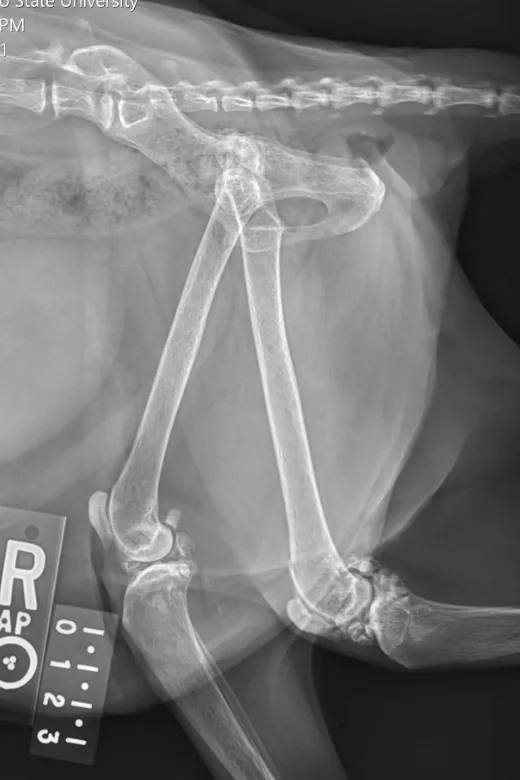

Radiographs taken by the referring clinician showed a shallow right acetabulum with decreased coverage of the femoral head and secondary changes, including a sclerotic acetabular rim, smoothly marginated periosteal proliferation along the cranial and caudal pillars of the acetabulum, flattening of the right femoral head, thickening of the femoral neck, and mild craniodorsal subluxation. The left coxofemoral joint was congruent but had mild changes with osteophytes along the cranial acetabular margin. There was a mild amount of spondylosis deformans at L6-L7 and L7-S1. Radiographs of the stifles showed subchondral bone sclerosis of both medial femoral condyles and medial tibial condyles. Osteophytes and enthesophytes were present along the distal femurs and proximal tibiae. A large amount of amorphous periarticular new bone was located within and adjacent to the craniomedial aspects of the stifle joints and just proximal to the tibial eminences. Radiographic diagnoses at that time were moderate, right-sided, coxofemoral degenerative joint disease with subluxation of the femoral head; mild, left-sided, coxofemoral degenerative joint disease with no evidence of subluxation; and severe, bilateral stifle degenerative joint disease.At the referral clinic, 8.5 months after initial presentation, Max was sedated, and repeat ventrodorsal and orthogonal lateral pelvic radiographs were obtained to evaluate progression or change (Figure).

Ventrodorsal and right lateral radiographic images of feline stifle demonstrating arthritic changes.

FIGURE 1

Ventrodorsal and lateral pelvic radiographs showing severe osteophyte formation along the right femoral head and neck that caused effacement of the trochanteric fossa. The acetabulum is shallow due to remodeling and osteophyte formation. Mild osteophyte formation remains along the left femoral head and neck, as well as moderate osteophyte formation along the acetabulum. Caudal lumbar spondylosis deformans is unchanged from initial radiographic findings. Rounded, angular mineral bodies are present bilaterally in the stifle joints with moderate concurrent periarticular osteophyte formation. Short, linear mineral bodies can be seen in the soft tissues of the right caudal crus.

Although findings were unchanged from previous radiographs, OA in the right hip appeared mildly progressed.